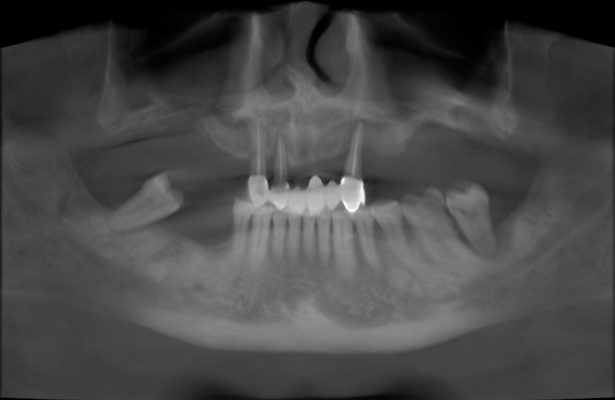

Qua thăm khám và chụp phim X-quang, đội ngũ bác sĩ tại Nha khoa Tâm Thiện Mỹ đánh giá trạng thái của bác Hải:

- Mất nhiều răng hàm trên, các răng còn lại ở trong bụi.

- Ảnh tới tính thẩm mỹ, chức năng ăn vỏ, gần như không thể nghiền nát.